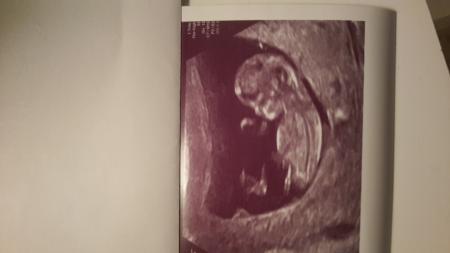

Bild zu

Hallo,ich würde nicht zwangsläufig von einem Jungen ausgehen. Unser Mädchen sah in der 12.SSW nicht sehr anders aus. LG, Anja

Jaa sieht man aber bei dir ist dünner ausgeprägt als bei meiner Foto, naja wie auch immer dan werde ich eben Mama von zwei Jungs Mehr weiss ich am Montag falls man was sieht Ich fand ein Ultraschalbild auf google das auch so ausieht sogar nochmehr sichtbarer und es kam beim Blutest wie ich lesen konnte ein Mädchen raus...